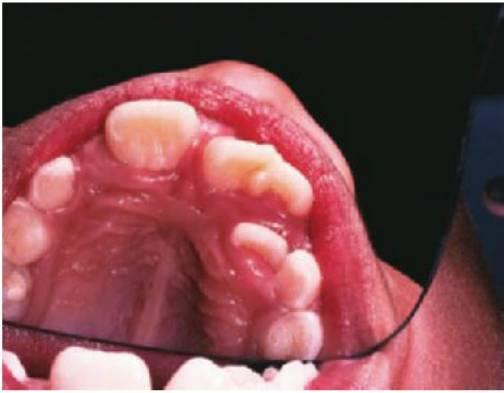

Los dientes supernumerarios surgen como resultado de una geminación de la lámina dental que se produce de forma esporádica o se heredan, como sucede con la displasia cleidocraneal (fig. 9.8).

La forma de los dientes puede recordar a la forma de las piezas normales (diente suplementario), es decir, incisiforme, caniniforme o molariforme; de no ser así, sería cónico o tuberculado.

Habitualmente se presenta como consecuencia del fallo en la erupción de uno o más dientes permanentes y en general presenta formas cónicas o tuberculadas.

- Erupción fallida o ectópica de un diente permanente (fig. 9.8B).

- A menudo erupcionan dientes cónicos que se pueden extraer con mucha facilidad (fig. 9.8A).

- Los dientes tuberculados o cónicos invertidos requieren extracción quirúrgica (fig. 9.8D) tan pronto como sea posible para permitir la erupción sin obstáculos del diente permanente.